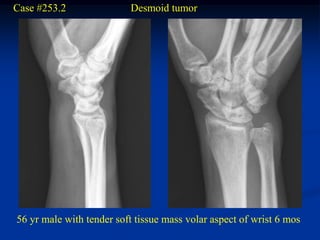

Case #253.2               Desmoid tumor

56 yr male with tender soft tissue mass volar aspect of wrist 6 mos